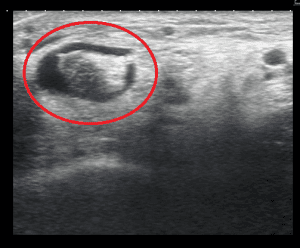

Ultrasound examination at The Foot and Ankle Centre can assist in diagnosing this problem. Below shows the position of the probe and the findings in posterior tibial tendon degeneration.

Probe positionNote the fluid surrounding the tendonFibres of the tendon are discontinuous

Ultrasound of tibialis posterior tendon Tibialis posterior tendinopathy ultrasound ultrasound result of posterior tibial tendon